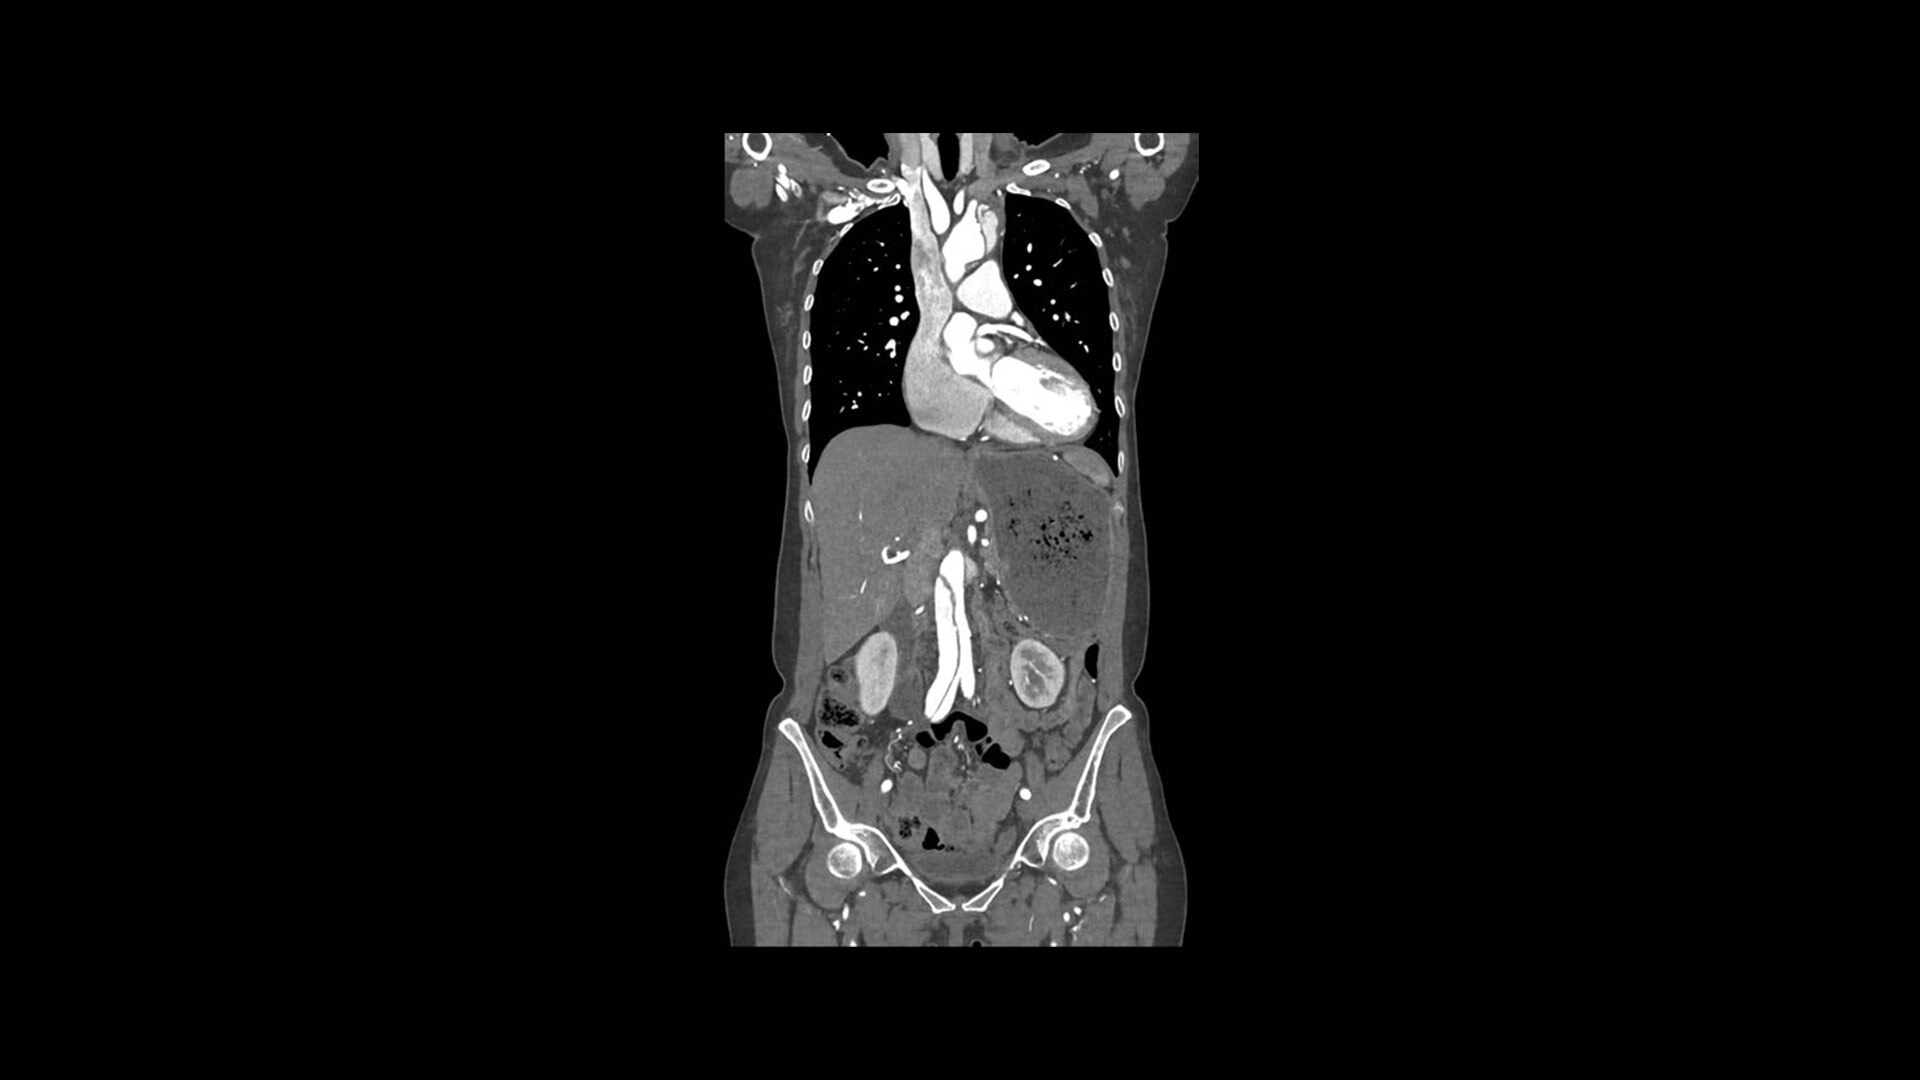

Introducing the new Revolution™ Ascend Platform, our latest CT offering designed to efficiently match your imaging demands. Whether you require a highly efficient system with 20 mm of coverage for routine scanning or a more advanced system with 40 mm of coverage that improves low contrast detectability, you can choose exactly what you need. Since the Revolution Ascend Platform is scalable, you can invest in the CT you need today and take comfort in knowing that it’s ready for tomorrow.

The Revolution Ascend Platform is ready for your CT department's clinical needs and efficiency demands. By offering advanced clinical capabilities, exceptionally efficient workflow as well as the latest in scalable imaging technology, you will have a CT that can keep you ahead of today's patients and tomorrow's challenges.

With the Revolution Ascend Platform, you can combine both of our AI-based imaging reconstruction technologies to create one stunning image. By combining True Enhance DL with TrueFidelity DL, you can achieve images that have less noise, enhanced sharpness and better noise texture than images obtained with ASiR-V.